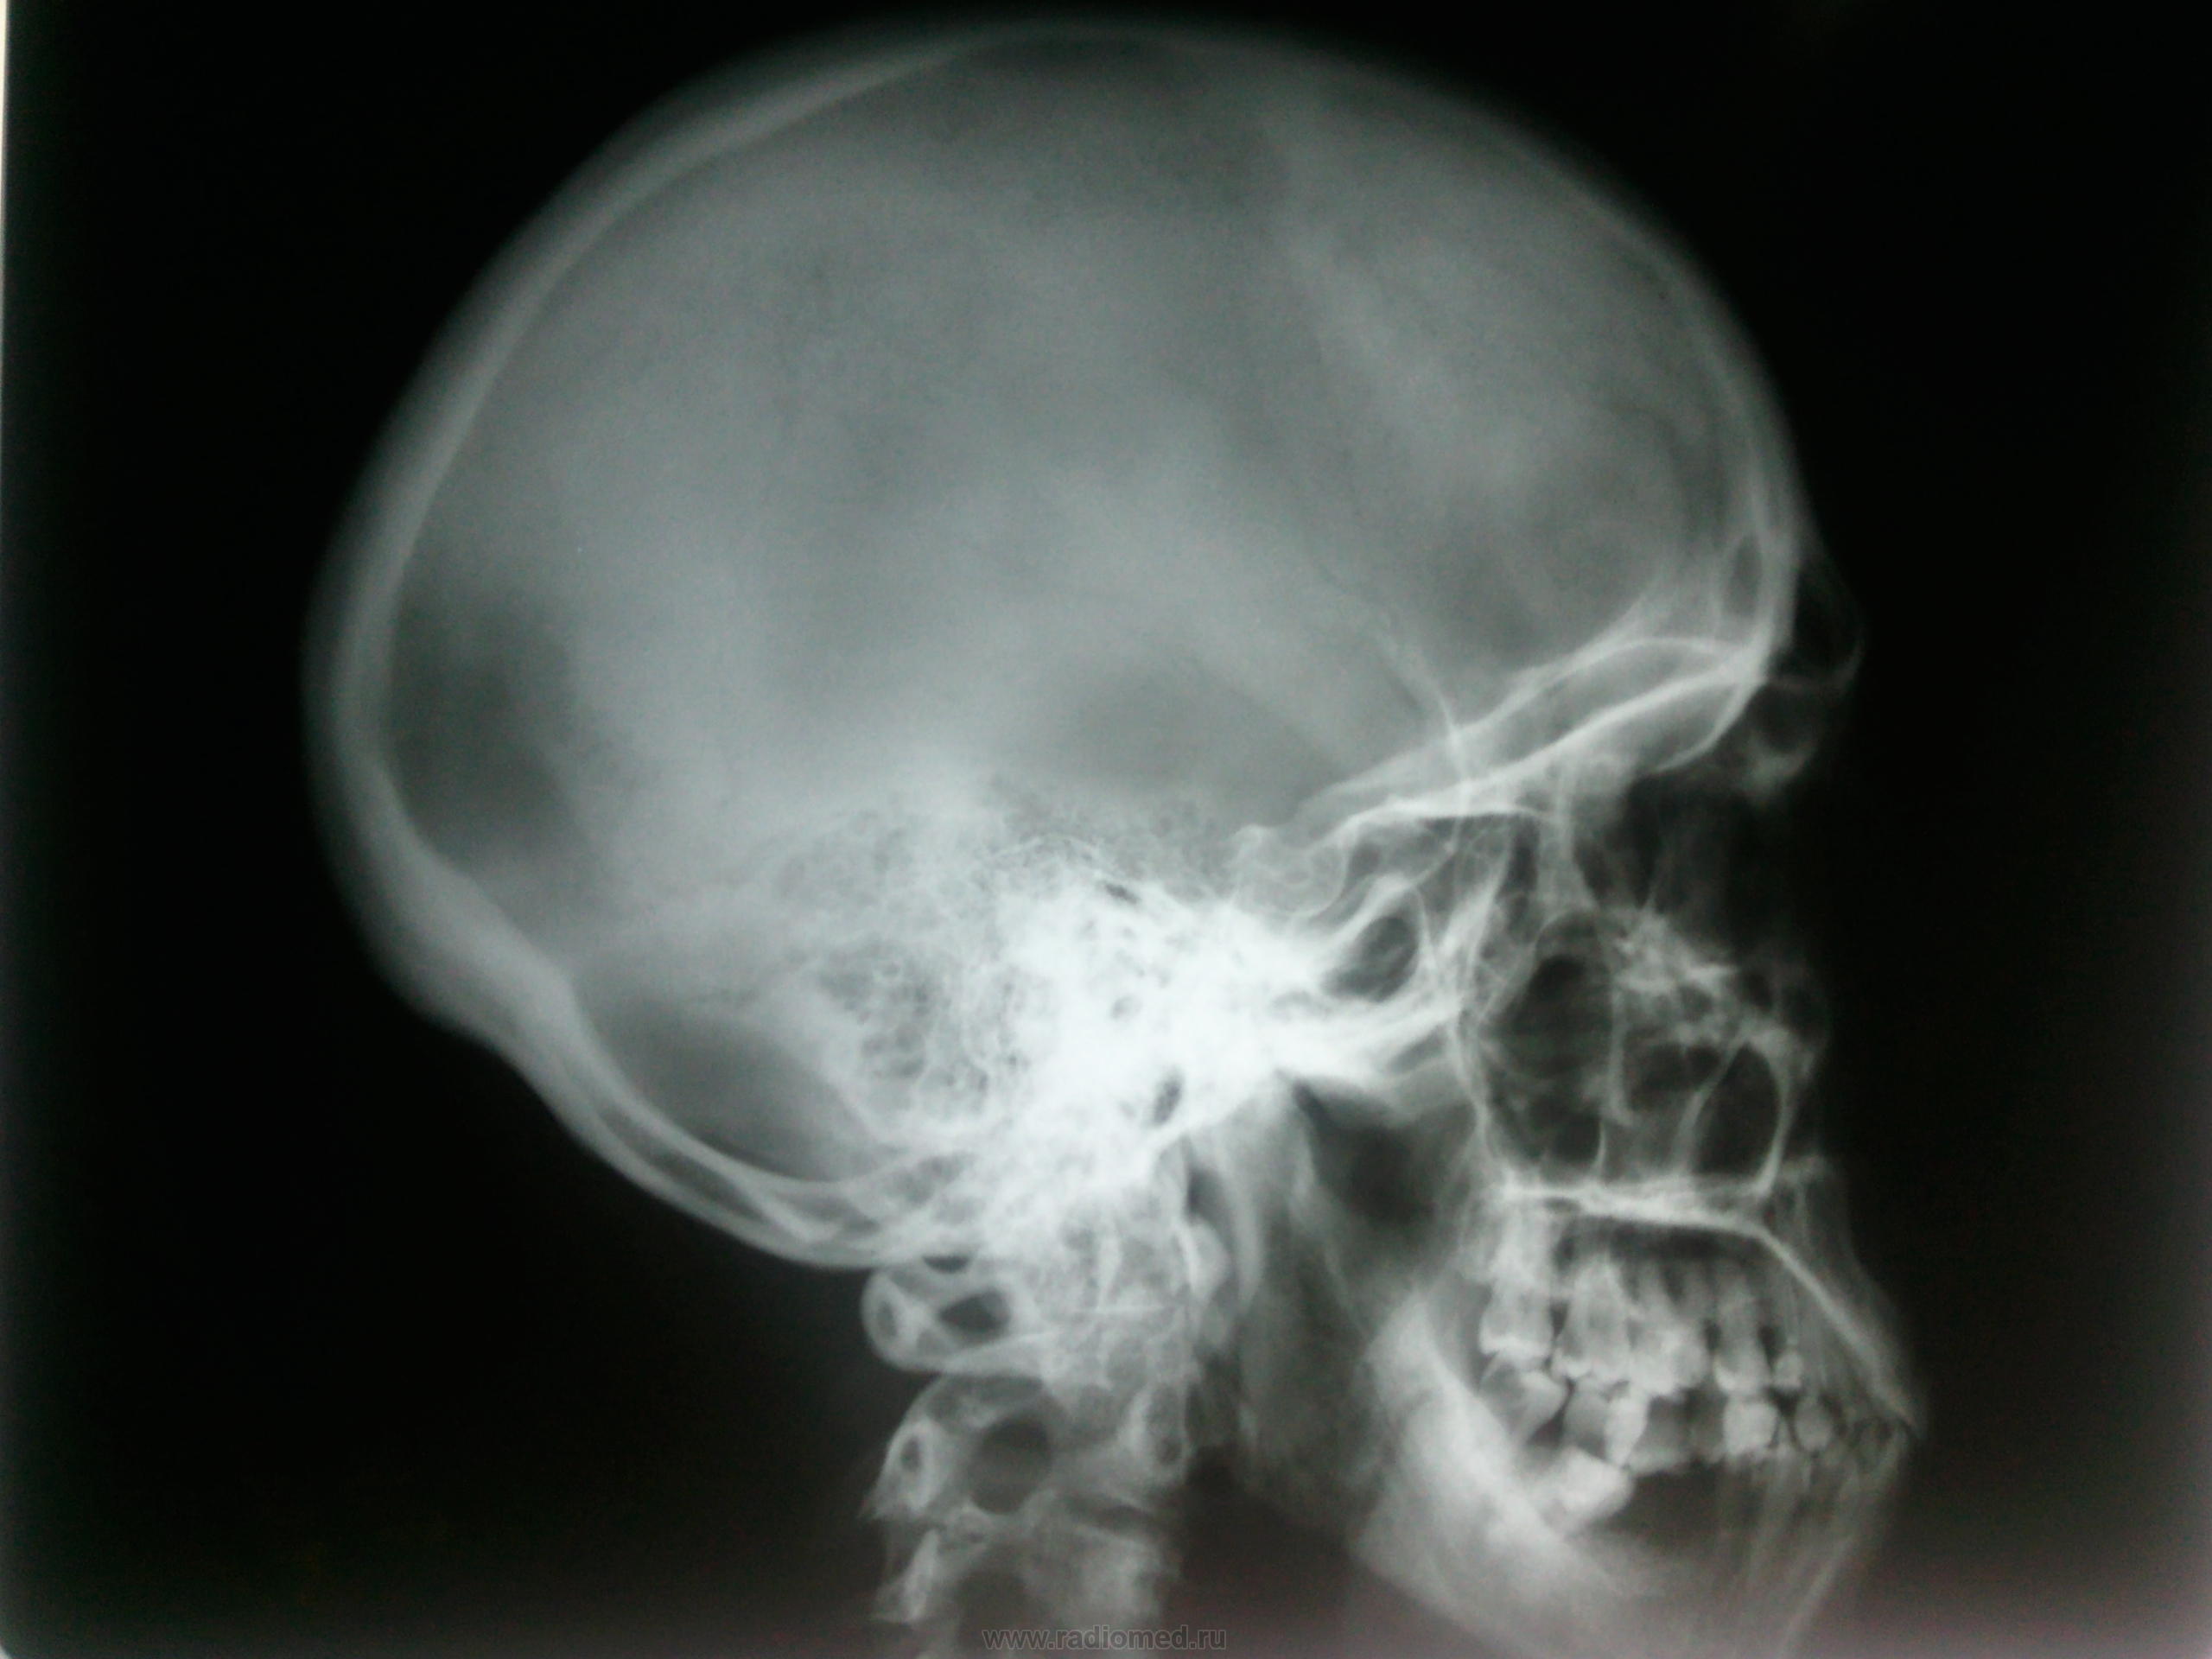

Пол пациента: Женский пол Тип патологии: Другое Область исследования: Череп и головной мозг Методы исследования: Rg Не могу понять, что с седлом? Или все же особенности укладки? https://radiomed.ru/sites/default/files/styles/case_slider_image/public/user/134/foto0318.jpg?itok=ONQ6m-EP ID:24784 Sat, 24/11/2012 - 18:19 #1 Любовь С. Offline Last seen: 9 years 11 months ago Joined: 23.12.2010 - 01:58 Posts: 2324 Ни седла, ни седока). Картинки вставьте, плиз)). "Предоставляя весь смысл и совершенство в распоряжение одного только Бога, вы избавляете себя от бездны хлопот." Джон Уитборн. Sat, 24/11/2012 - 19:49 #2 Тарелка Offline Last seen: 10 years 6 months ago Joined: 23.06.2008 - 23:11 Posts: 108 Попытка № 2Приложения: Sat, 24/11/2012 - 20:00 #3 stovbav Offline Last seen: 2 years 8 months ago Joined: 20.12.2009 - 17:28 Posts: 7066 Для ТАКОГО седла разьезд при укладке великоват будет... Болезни ног: виды, симптомы, причины, профилактика и лечение Sat, 24/11/2012 - 20:16 #4 Nela Offline Last seen: 6 years 6 months ago Joined: 12.05.2009 - 20:43 Posts: 1847 Скорее всего обызвествление стенок сифонов внутренних сонных артерий. Лет-то сколько седлу? Sat, 24/11/2012 - 20:19 #5 И.Бондаренко Offline Last seen: 1 day 12 hours ago Joined: 13.09.2011 - 22:55 Posts: 9214 Скорее всего обычные обызвествления диафрагмы. Желательно переснять с нормальной укладкой, и диафрагмирование. Sat, 24/11/2012 - 21:01 #6 Тарелка Offline Last seen: 10 years 6 months ago Joined: 23.06.2008 - 23:11 Posts: 108 38 лет Sat, 24/11/2012 - 21:26 #7 Андрей Юрьевич Offline Last seen: 4 weeks 1 day ago Joined: 16.11.2008 - 22:16 Posts: 18106 Тогда, плюсую к И.Бондаренко по дообследованию, прицельно с двух сторон. Может вообще ничего не быть. Андрей Юрьевич Sat, 24/11/2012 - 22:06 #8 Nela Offline Last seen: 6 years 6 months ago Joined: 12.05.2009 - 20:43 Posts: 1847 Скорее всего ничего и не будет, но можно и томограммы сделать. Mon, 26/11/2012 - 22:20 #9 maker4ik Offline Last seen: 9 years 1 week ago Joined: 19.10.2011 - 17:49 Posts: 2682 Мне кажется, надо укладку поровнее. Tue, 27/11/2012 - 00:55 #10 Петрович Offline Last seen: 7 years 8 months ago Joined: 22.03.2009 - 01:13 Posts: 3908 Там, наверное, асимметрия черепа есть... На другой бок. Неоднозначно всё

Скорее всего обызвествление стенок сифонов внутренних сонных артерий. Лет-то сколько седлу?

Скорее всего обычные обызвествления диафрагмы. Желательно переснять с нормальной укладкой, и диафрагмирование.

38 лет

Тогда, плюсую к И.Бондаренко по дообследованию, прицельно с двух сторон. Может вообще ничего не быть.

Скорее всего ничего и не будет, но можно и томограммы сделать.

Мне кажется, надо укладку поровнее.

Там, наверное, асимметрия черепа есть... На другой бок.